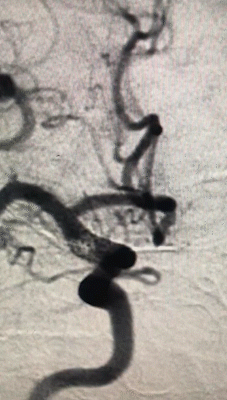

3.1)

回撤到平直段,半释放pipeline

3.2)

Navien继续上高,推支架,确保瘤颈处支架的贴壁